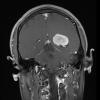

NEOPLASMS (MENINGIOMA)

Brain Invasion (7)